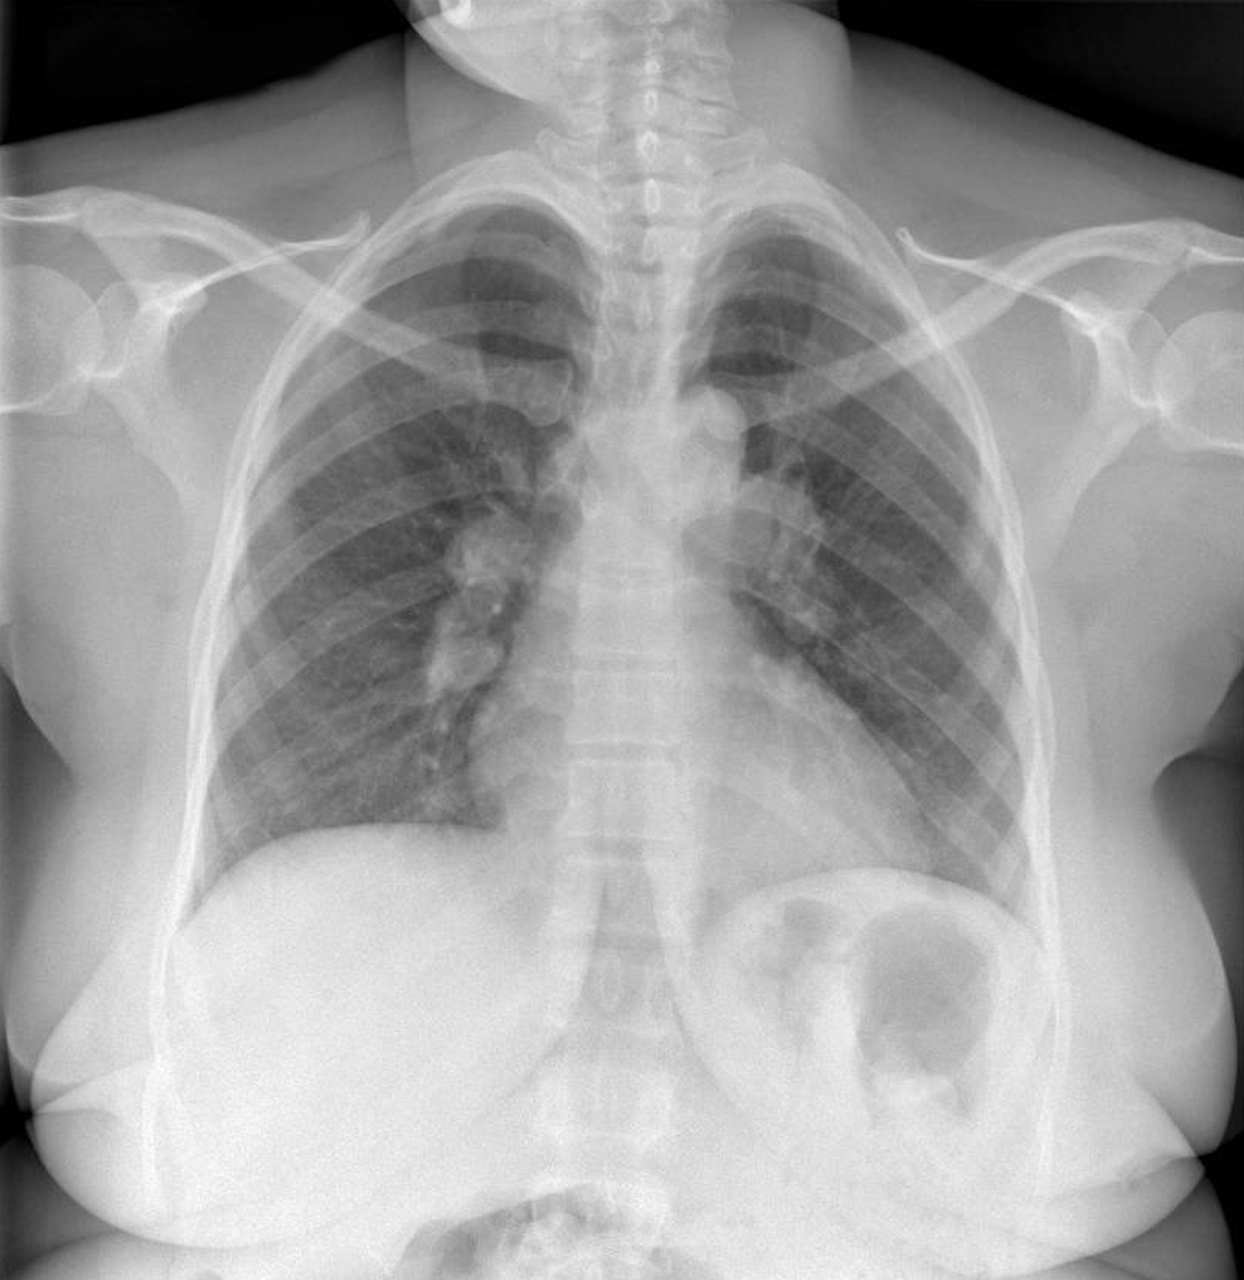

Le syndrome de Löfgren associe un érythème noueux, une bi-arthrite de chevilles et des adénopathies médiastinales.